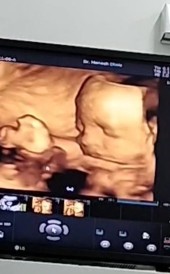

มาอวดรูปลูกชายครับ

คุณพ่อคุณแม่ท่านไหนเห็นหน้าน้องชัดกันแล้วบ้างมาอวดรูปลูกกันครับ